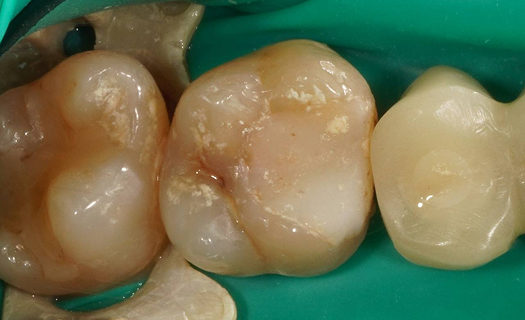

Лечение: Проведено эндодонтическое перелечивание зуба под дентальным микроскопом, что позволило точно выявить анатомические особенности корневых каналов и устранить последствия ранее некачественного лечения. После купирования воспалительного процесса (киста) каналы герметично запломбированы. Коронковая часть зуба восстановлена для сохранения функции и герметичности до этапа постоянного протезирования.

Результат: После проведённого лечения болевые ощущения полностью устранены, отёк щеки исчез, воспалительный процесс купирован. Зуб сохранён, восстановлена его функция. Установлена коронка, что позволило полностью восстановить анатомическую форму и жевательную эффективность зуба.